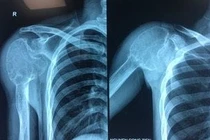

(khoahocdoisong.vn) - Các bác sĩ Trung tâm Chấn thương chỉnh hình và Y học thể thao Vinmec đã thực hiện thành công ca phẫu thuật phức tạp cắt khối nang xương phình mạch có kích thước lớn phá vỡ hết cấu trúc xương đầu trên xương cánh tay phải và thay toàn bộ phần xương cánh tay khuyết hổng bằng kỹ thuật thay khớp vai đảo ngược.